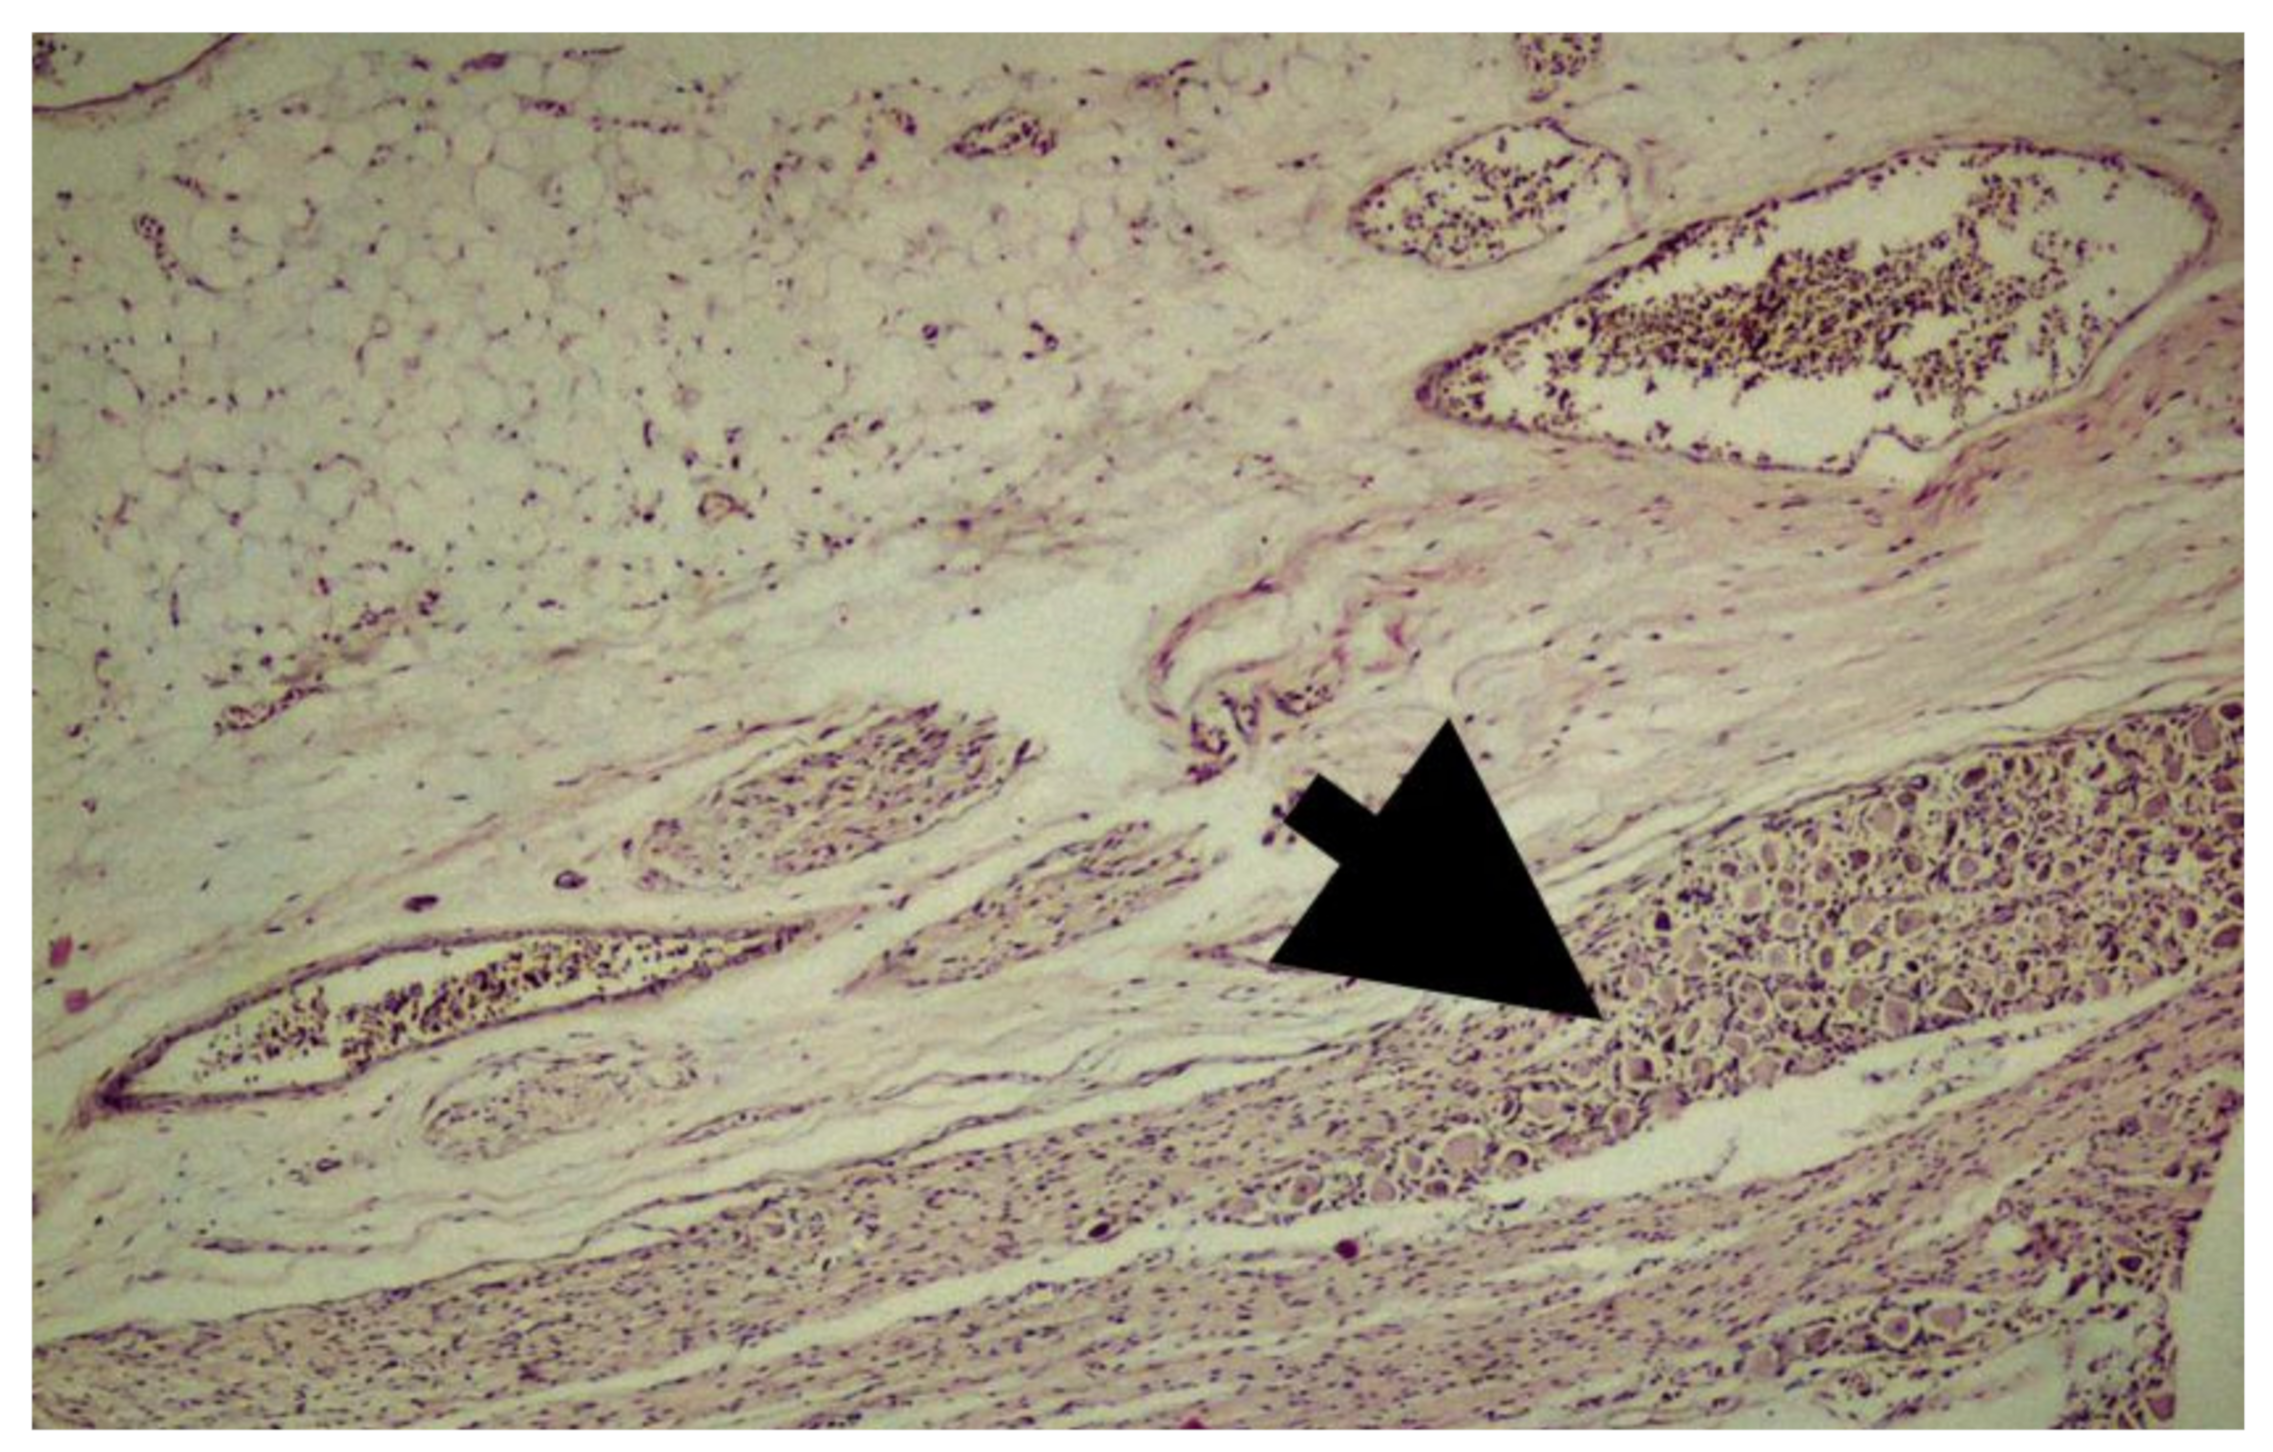

Figure 4.

Fetal filum terminale composed of peripheral nerve and ganglion cells along with adipose and connective tissue (H&E, ×40). Thick black arrow indicates nerve ganglion bundle.